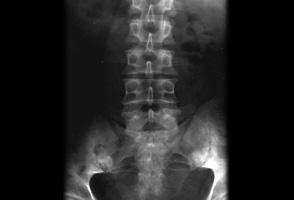

მიმოხილვითი რენტგენი, რომელიც გვიჩვენებს ბილატერალურ საკროილიიტს მაანკილოზებელი სპონდილიტის მქონე პაციენტში

BMJ 2006;333;581-585. © BMJ Publishing Group Ltd 2009